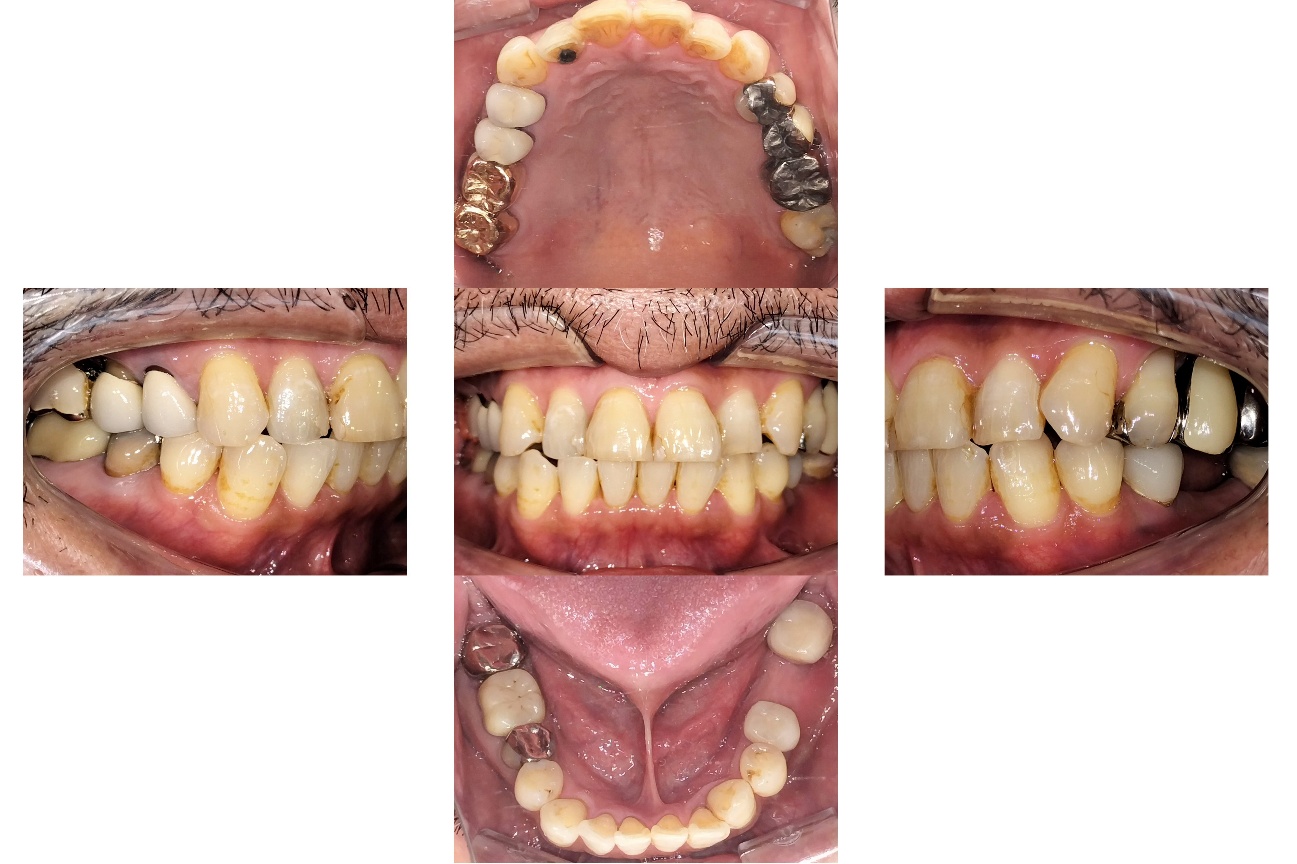

インビザラインによる全体矯正後に補綴治療を行い、咬合と審美性を総合的に改善した症例です。

まずマウスピース型矯正装置(インビザライン)により歯列および咬合関係を整え、その後、必要部位にジルコニア補綴を行いました。

矯正のみ・補綴のみではなく、両治療を組み合わせることで機能性と審美性の両立を目指した包括的治療です。

患者様は、奥歯でしっかり噛めないことと、前歯の歯並びの乱れを気にされ来院されました。診査の結果、前歯部の叢生(歯並びの乱れ)と、臼歯部の離開咬合(奥歯がしっかり噛み合っていない状態)が認められました。また、臼歯部には古い金属修復物が装着されており、機能面だけでなく審美面においても改善が必要な状態でした。

前歯の歯並びが整い、見た目の改善が認められました。また、奥歯でしっかり噛める状態となり、咬合機能の回復が得られています。

本症例では、歯並びの改善だけでなく、噛み合わせの回復と審美性の向上を同時に行っています。当院は一般歯科と矯正治療の両方に対応しているため、矯正治療後に別の医療機関で補綴治療を行う必要がなく、一貫した治療計画のもとで治療を完結することが可能です。また、奥歯の噛み合わせを矯正治療のみで改善する場合、治療期間が長くなることがありますが、本症例では補綴治療(アンレー)を併用することで、比較的短期間で咬合の改善を行いました。さらに、古い金属修復物をジルコニアに置き換えることで、見た目の改善と機能性の両立を図っています。